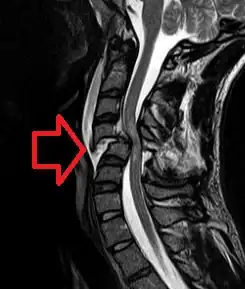

| Cervical spine MRI showing a C4 fracture and dislocation resulting in spinal cord compression | |